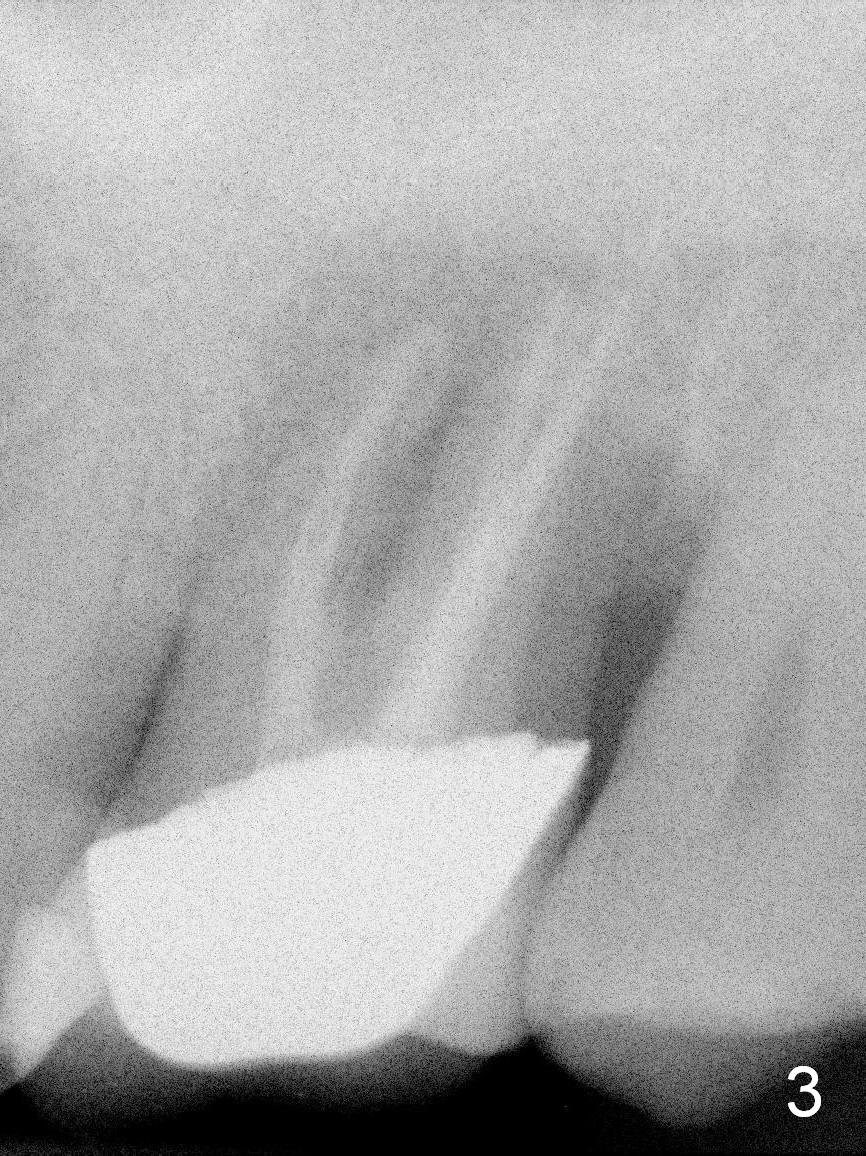

A 56-year-old woman has had sign of root fracture at the site of 15 for the last 3 years (Fig.2,3), 5 years after RCT (Fig.1). It appears that the sinus floor is around 1 mm and consists of the cortical bone (Fig.2). After extraction and Clindamycin disinfection, IBS Sinus Lifter (2 3) will be used, followed by allograft placement, 4.3 mm long drill, and 5x9 mm dummy implant. Take PA and measure depths relative to the sinus floor and crest. Prepare latch and hand implant drivers as well as calibrated torque wrench. Amalgam and large bone carriers should be available. Although primary stability is expected to be low, an immediate provisional should be fabricated with sufficient occlusal clearance. Since the bone density is high, use higher voltage to take X-ray.